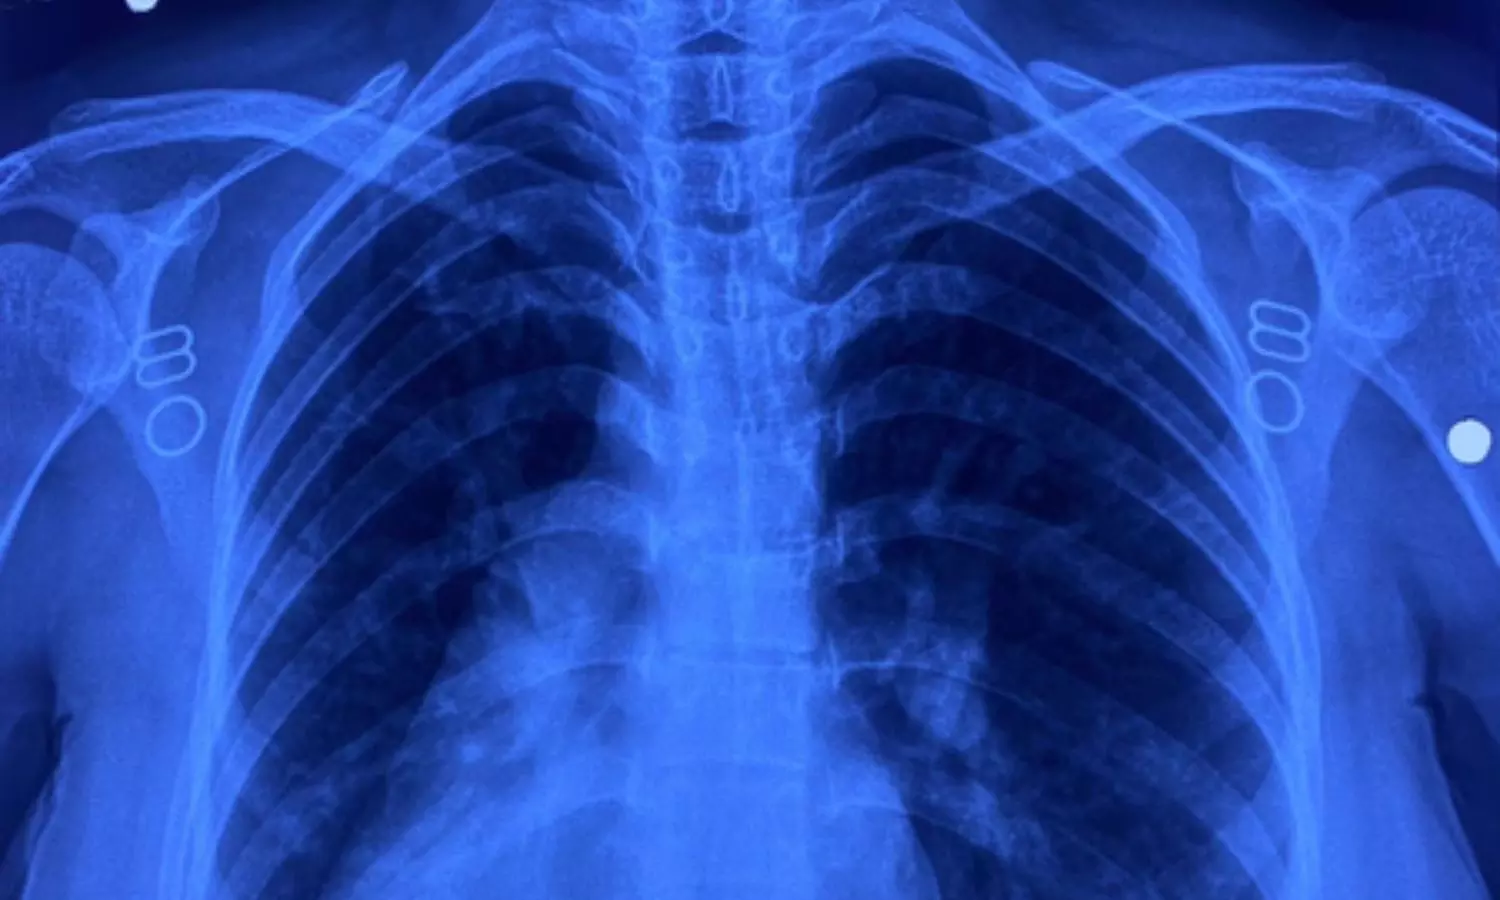

इस मरीज के सभी अंग सामान्य जगह के उलट यानी मिरर इमेज में थे। उसके दिल की जगह दाईं ओर थी, लिवर बाईं ओर, प्लीहा दाईं ओर और पेट भी दाईं ओर था। इसके साथ ही मरीज में जन्मजात आंशिक एट्रियोवेंट्रिकुलर कैनाल दोष जैसी जन्मजात हृदय रोग की समस्या भी थी।

सर्जरी के दौरान चिकित्सा टीम ने अत्यंत सावधानी बरतते हुए मरीज के हृदय दोष का सफल उपचार किया। मात्र 4 सेंटीमीटर के सूक्ष्म 'इन्फ्रामैमरी' चीरे के जरिए यह जटिल प्रक्रिया संपन्न की गई। ऑपरेशन के दौरान हृदय की कार्यप्रणाली को सुचारू रखने के लिए शरीर की बाहरी नसों की सहायता से 'कार्डियोपल्मोनरी बाईपास मशीन' का उपयोग किया गया।

हृदय के दोष को ठीक करने के लिए मरीज की अपनी 'पेरिकार्डियम' (हृदय की सुरक्षा झिल्ली) से पैच तैयार किया गया और उसे बेहद बारीक टांकों के जरिए सटीक स्थान पर लगाया गया, ताकि हृदय के वाल्व और कंडक्शन सिस्टम को कोई क्षति न पहुंचे। सर्जरी के बाद मरीज की रिकवरी बहुत ही सहज रही और अब वह अस्पताल से जाने के लिए पूरी तरह फिट है। इकोकार्डियोग्राफी ने भी सफल सर्जरी की पुष्टि की।

इस सर्जरी में कई चुनौतियां थीं। सबसे बड़ी चुनौती यह थी कि जन्मजात हृदय दोष, वाल्व और संवेदनशील कंडक्शन सिस्टम के अत्यंत निकट था। इसके अतिरिक्त, रक्त वाहिकाओं की 'मिरर इमेज' (विपरीत दिशा) स्थिति ने सर्जरी को और भी पेचीदा बना दिया था। महज 4 सेंटीमीटर के छोटे चीरे के माध्यम से उपकरणों को संभालना और सूक्ष्म टांके लगाना तकनीकी रूप से बेहद कठिन कार्य था। मरीज को हृदय–फेफड़ों की मशीन के माध्यम से बायपास करना पड़ा, जिससे टीम की विशेषज्ञता और अनुभव की जरूरत थी।